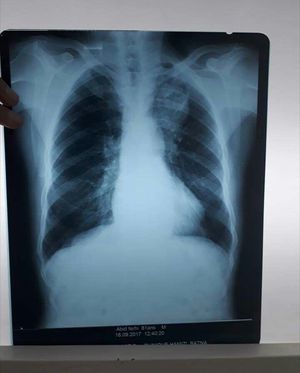

age 81 years old smoking since 1948 Left scapular pain dyspnea, BK negative, productive cough, whitening sputum